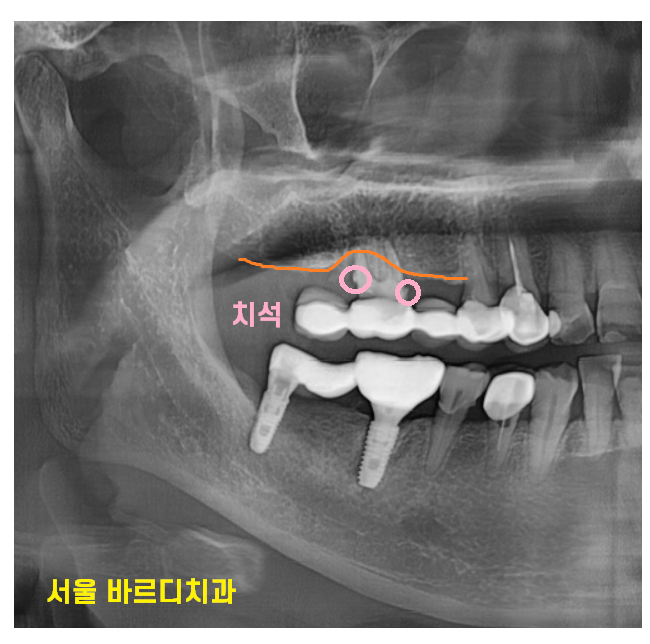

풍산동 치과에서 ct를 찍어보니

뿌리 흡수도 심하고

갈라지는 부분에 뼈도 많이 녹아있었거든요.

풍산동 치과에서 발치 후 임플란트 수술을

진행하셨습니다.